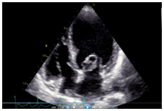

Her echocardiogram showed mild left ventricular and left atrial dilatation with normal left ventricular systolic function. The mitral valve was morphologically abnormal with the anterior mitral leaflet showing an cystic aneurysmal segment with systolic ballooning and some degree of diastolic collapse but incomplete collapse. (Figures 1-3) (Video 1) (Video 2) The aneurysmal segment showed a classical heart shape which was most evident in the end systolic frame. Colour flow imaging showed severe mitral regurgitation with an eccentric jet, the origin of the jet appeared to be through the anterior mitral leaflet. The transeosopheal echocardiography revealed similar findings (Figure 4) (Figure 5)The aortic valve was morphologically normal but for mild cuspal thickening.

Figure 3 The cystic mass appearing like a heart in the parasternal long axis view on echocardiography.